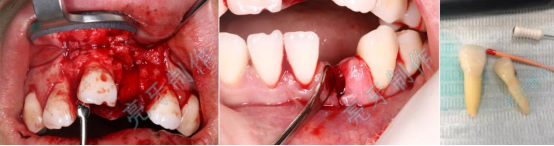

病例三:牙齿嵌入牙槽骨,松动明显,经过治疗,稳定了,也恢复了外形。

病例四:右侧前牙牙齿嵌入牙槽骨,无法咬合,治疗后,恢复功能和外形。